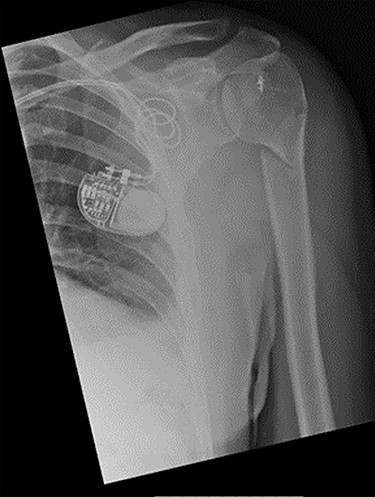

Examination and imaging of the patient revealed that during the fall, he had sustained a left surgical neck of humerus fracture (Fig. 1). Significant skin puckering was noted on the anterior aspect of the left shoulder over the fracture site, otherwise the arm was neurovascularly intact (Fig. 2). He was immediately reviewed by the orthopaedic team who offered surgical fixation of the fracture on the following morning, which was dependent on an appropriate anaesthetic assessment. The patient was in agreement and consented to proceed.

Antero-posterior view X-ray taken on day of admission, showing a left surgical neck of humerus fracture with anterior displacement of the proximal humeral shaft.